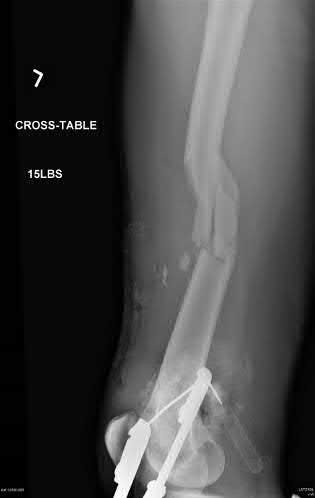

A 62-year-old male with multiple myeloma presents with thigh pain. Radiographs demonstrate an osseous lesion. When calculating the Mirels' score to determine the indication for prophylactic internal fixation, which of the following clinical or radiographic findings assigns the maximum of 3 points for its respective category?

Explanation

The Mirels' classification evaluates four parameters to predict impending pathologic fracture: Site (Upper extremity=1, Lower extremity=2, Peritrochanteric=3), Pain (Mild=1, Moderate=2, Functional/Severe=3), Lesion character (Blastic=1, Mixed=2, Lytic=3), and Lesion size (<1/3 cortex=1, 1/3 to 2/3 cortex=2, >2/3 cortex=3). A score of 9 or greater indicates impending fracture requiring prophylactic fixation. Therefore, a lesion >2/3 of the cortex scores 3 points.